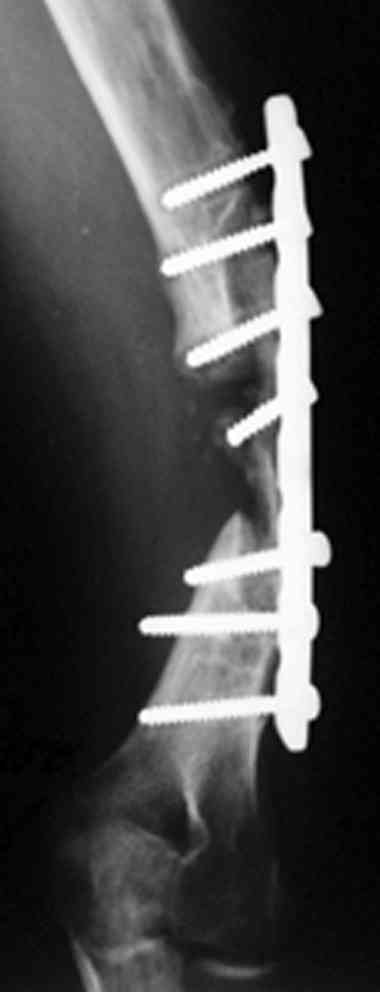

Рентгеновская версия реконструкции. хронология:

после операции, 2 мес. после операции, через 1 год

Движения в полном объеме восстановлены к 2 мес. после операции. Если надо могу показать мультик. Сейчас уже прошло более 3 лет, больная не

показывается. Успехов ЛАФ.